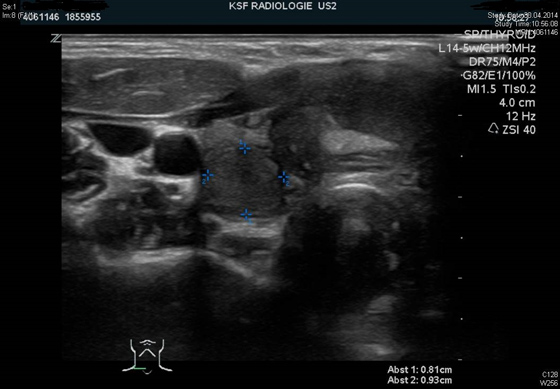

• Sonographie (Ultraschall) der Schilddrüse

Diese ermöglicht die Beurteilung der Grösse der Schilddrüse, sowie verdächtiger Knoten.